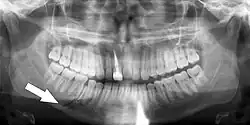

Simple mandible fracture